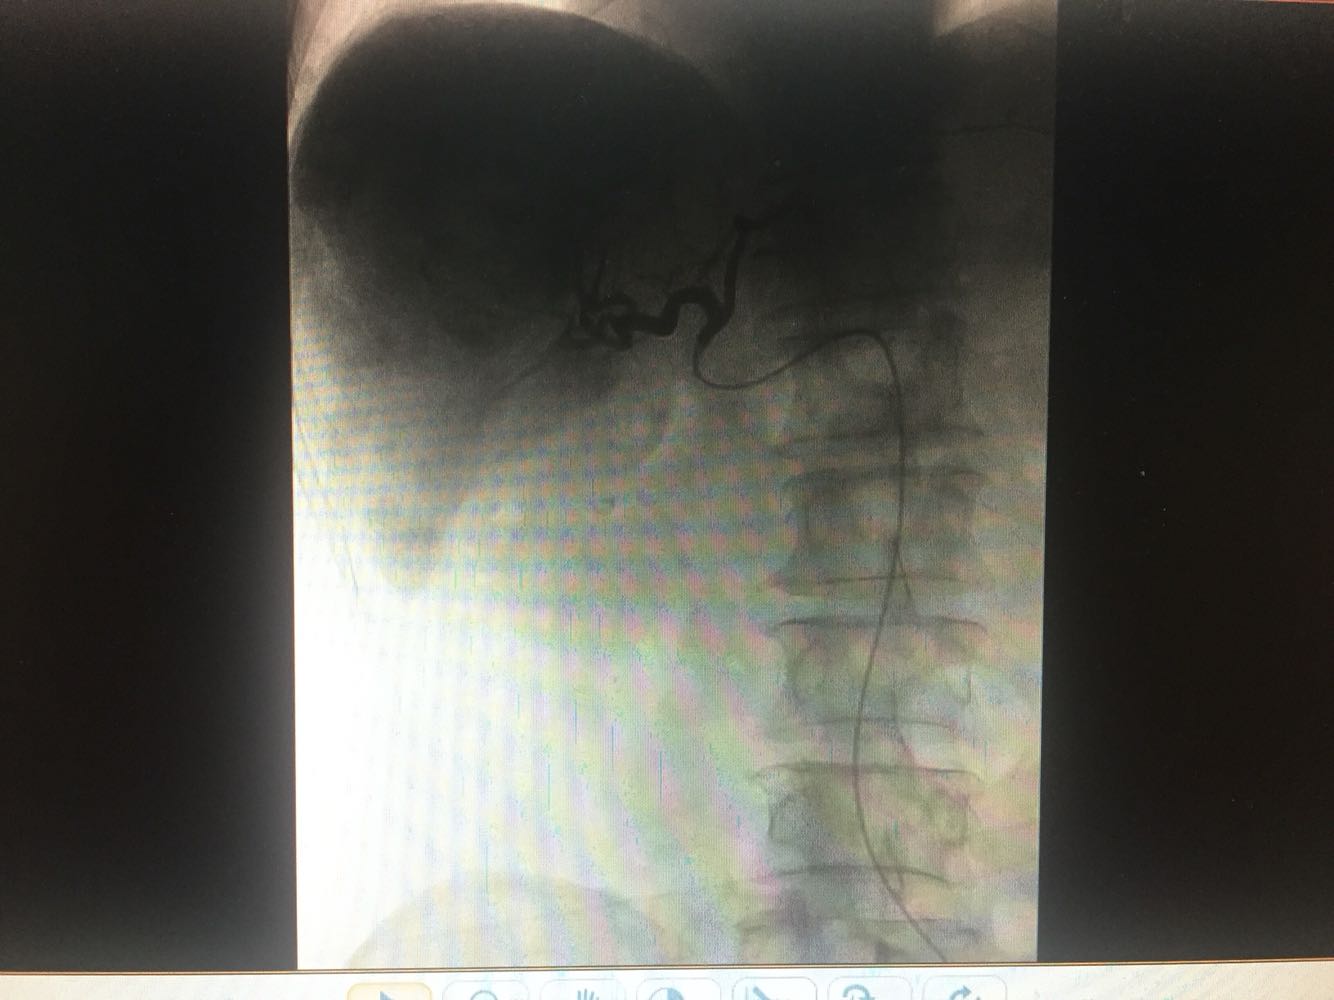

查体:体温,36摄氏度,脉搏:60次/分,呼吸,19次/分、血压,115/70mmhg,发育正常,营养欠佳,皮肤黏膜,色泽正常,双侧眼睑正常,双侧巩膜无黄染,口唇红润,双肺呼吸音清晰,心率60次/分,心律齐,心音有力,无病理性杂音。右上腹部饱满,中上腹压痛明显,肝脏肋下2cm触及,质地硬,触痛阳性,脾肋下2cm触及,移动性浊音阴性,肠音正常,双下肢无水肿 化验:血常规:白细胞计数2.9*10~9/L,中性粒细胞1.4*10~9L,红细胞计数4.03*10^12L,血小板计数76*10^9/L;生化全套。血糖4.67mol/L,总蛋白81.0g/L,白蛋白40.9g/1L,丙氯酸氨基转移酶256U/L,天门冬氨酸氨基转移酶182U,总胆红素22.0umol/L,胆碱酯酶4479U/L,Y-谷氨酰基转移酶137U/L;传染病9项:乙型肝炎病表面抗原阳性/6380,乙型肝炎病毒e抗体阳性/0.004,乙型肝炎病毒核心抗体阳性/0.008 肿瘤标志物:甲胎蛋白415.50ng/ml,乙型肝炎病毒DNA测定2.06E+07IU/ml CT:1.考虑肝右叶巨块型肝癌伴肝内多发转移,2.肝门部及腹膜后、心隔角旁小淋巴结。3.肝小囊肿。4.肝左叶増大。5.肝脏钙化灶。6.副牌。7.双肾微小囊肿

乙肝肝硬化,原发性肝癌,保肝抗病毒治疗,及TACE

出院一月后复查,行增强CT扫描,肿瘤明显缩小,肝功能正常,乙肝病毒复制转阴,建议继续口服恩替卡韦抗病毒治疗